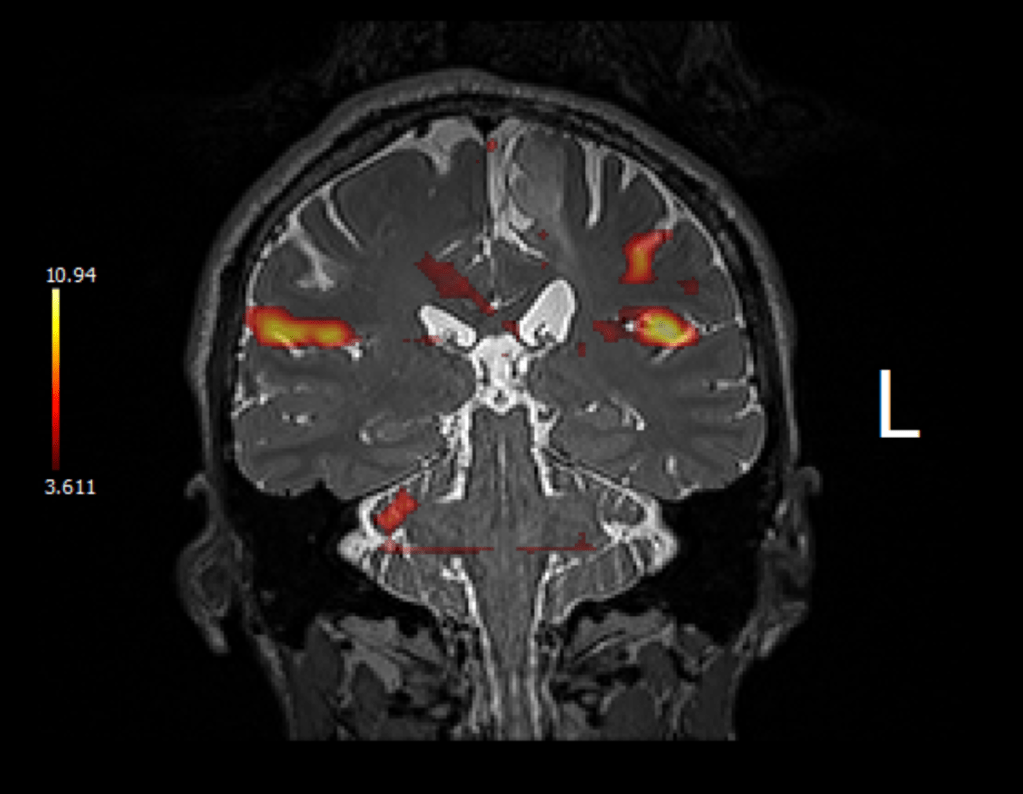

Interesting fMRI pictures (interesting note is that I was able to obtain these myself using my patient portal and scrolling through the MRI test!):

Image of my facial muscles working on both sides: